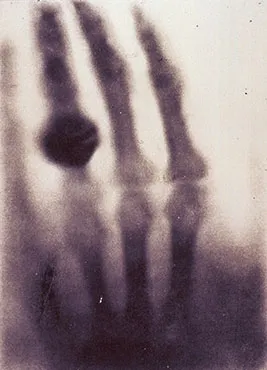

5. Wilhelm Röntgen: X-rays.

Mysterious short-wavelength rays of an unknown type (therefore designated X) emerged when Röntgen shot cathode rays (beams of electrons) through a glass tube. Röntgen suspected that his creation might be a new kind of wave among the many Maxwell had anticipated: “There seems to exist some kind of relationship between the new rays and light rays; at least this is indicated by the formation of shadows,” Röntgen wrote. Those shadows, of course, became the basis for a revolutionary medical technology.

Besides providing a major new tool for observing shattered bones and other structures inside the body, X-rays eventually became essential tools for scientific investigation in astronomy, biology and other fields. And they shattered the late 19th century complacency of physicists who thought they’d basically figured everything out about nature. Weirdly, though, X-rays later turned out to be particles sometimes, validating Einstein’s ideas that light had an alter ego particle identity. (By the way, it turned out that X-rays aren’t the electromagnetic waves with the shortest wavelengths — gamma rays can be even shorter. Maybe they would be No. 11.)